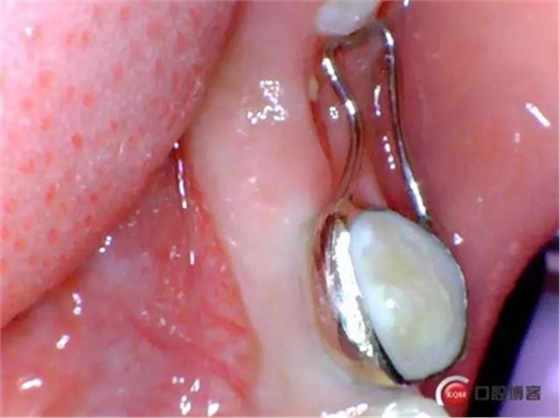

一周后患者復(fù)診,拔牙創(chuàng)恢復(fù)良,制作*74口內(nèi)帶環(huán)并焊接,反復(fù)試戴合適后藻酸鹽取上下頜模型并發(fā)加工廠做保持器。電話預(yù)約復(fù)診時(shí)間。

保持器回來后電話預(yù)約患者復(fù)診,反復(fù)試戴合適后消毒隔濕干燥,常規(guī)富士Ⅸ粘結(jié)保持器,調(diào)合,拋光,囑患者注意口腔衛(wèi)生并預(yù)約半年復(fù)查一次。